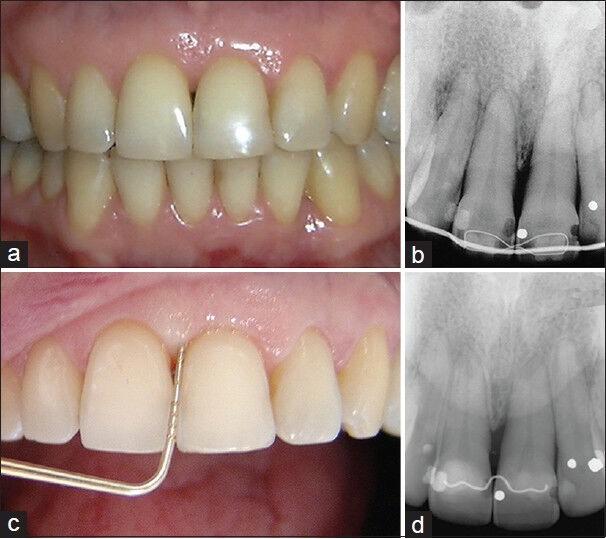

Extensive intraosseous lesions represent a clinical challenge for the periodontist. Sites with bone defects have been shown to be at higher risk of periodontitis progression in patients who had not received periodontal therapy. Thus, the aim of this case report was to describe a novel approach for the treatment of 1-walled intraosseous defect by combining nonsurgical periodontal therapy and orthodontic movement toward the bone defect, avoiding regenerative and surgical procedures. A 47-year-old woman underwent the proposed procedures for the treatment of her left central incisor with 9 mm probing depth and 1-walled intraosseous defect in its mesial aspect. Initially, basic periodontal therapy with scaling and root planning was accomplished. Two months later, an orthodontic treatment was planned to eliminate the intraosseous lesion and to improve the interproximal papillary area. Orthodontic root movement toward the osseous defect was performed for 13 months with light forces. After 6 years postoperative it was concluded that combined basic periodontal therapy and orthodontic movement was capable of eliminating the intraosseous defect and improve the esthetics in the interproximal papillary area between the central incisors.

广泛的骨内病变对牙周病医生来说是一项临床挑战。对于未接受过牙周治疗的患者,存在骨缺损的部位已被证明牙周炎进展的风险更高。因此,本病例报告的目的是描述一种通过结合非手术牙周治疗和向骨缺损处的正畸移动来治疗单壁骨内缺损的新方法,避免使用再生和外科手术。一名47岁女性接受了针对其左中切牙的拟议治疗程序,该牙探诊深度为9mm,近中面存在单壁骨内缺损。最初,完成了刮治和根面平整的基础牙周治疗。两个月后,计划进行正畸治疗以消除骨内病变并改善邻间隙乳头区域。使用轻力向骨缺损处进行正畸牙根移动13个月。术后6年得出结论,基础牙周治疗和正畸移动相结合能够消除骨内缺损并改善中切牙之间邻间隙乳头区域的美观。